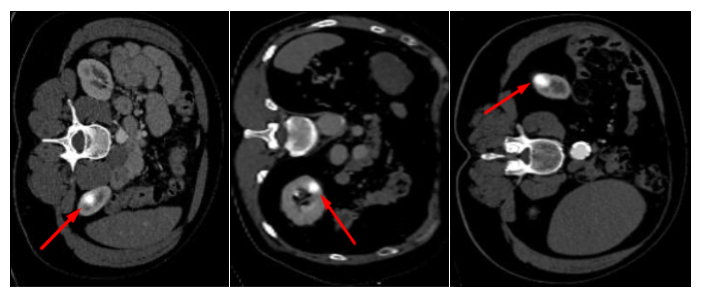

Refer to caption

Figure 3: Examples of the synthetic anomalies injected randomly inside kidneys for the TotalSegmentator dataset.

In order to establish a robust benchmark for assessing the performance of the modeling decisions, this research introduces a synthetic anomaly, meticulously designed and integrated into the CT scans datasets. The synthetic anomaly is conceptualized as a Gaussian blob, characterized by a fixed sigma and radius. This design choice is deliberate, aiming to mimic typical radiological findings that present as circular or ellipsoid structures in medical imaging. The synthetic anomaly is sampled at random positions within one of the kidneys in the abdominal slices of the scans in the TotalSegmentator dataset. This approach ensures a diverse and unpredictable distribution of anomalies, closely simulating the randomness and variability. To further enhance the complexity and variability of the synthetic anomaly, a series of transformation and augmentation techniques are employed, including random grid distortions, scaling and rotations. The examples of resulting gaussian blobs are visualized in Figure 3.